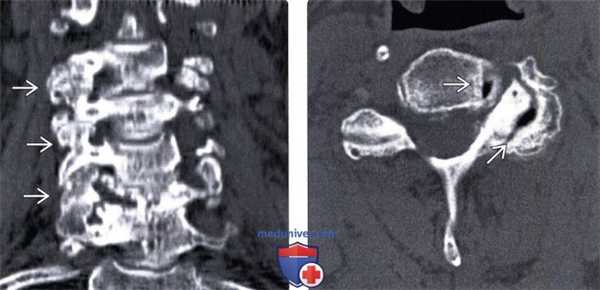

(Слева) КТ, фронтальный срез: признаки выраженной многоуровневой дегенеративной гипертрофической артропатии дугоотростчатых суставов с фораминальным стенозом.

(Справа) КТ, аксиальный срез: признаки выраженного дегенеративного поражения левого дугоотростчатого сустава и фораминального стеноза. В полости дугоотростчатого и унковертебрального сустава отмечается «феномен вакуума».

(Слева) На корональной КТ без КУ определяется тяжелая многоуровневая гипертрофическая дегенеративная артропатия дугоотростчатых суставов со стенозом межпозвонковых отверстий.

(Справа) На аксиальной КТ без КУ определяется тяжелая левосторонняя дегенеративная артропатия дугоотростчатого сустава со стенозом межпозвонкового отверстия. Определяется вакуум - феномен дугоотростчатого сустава и унковертебрального сустава.